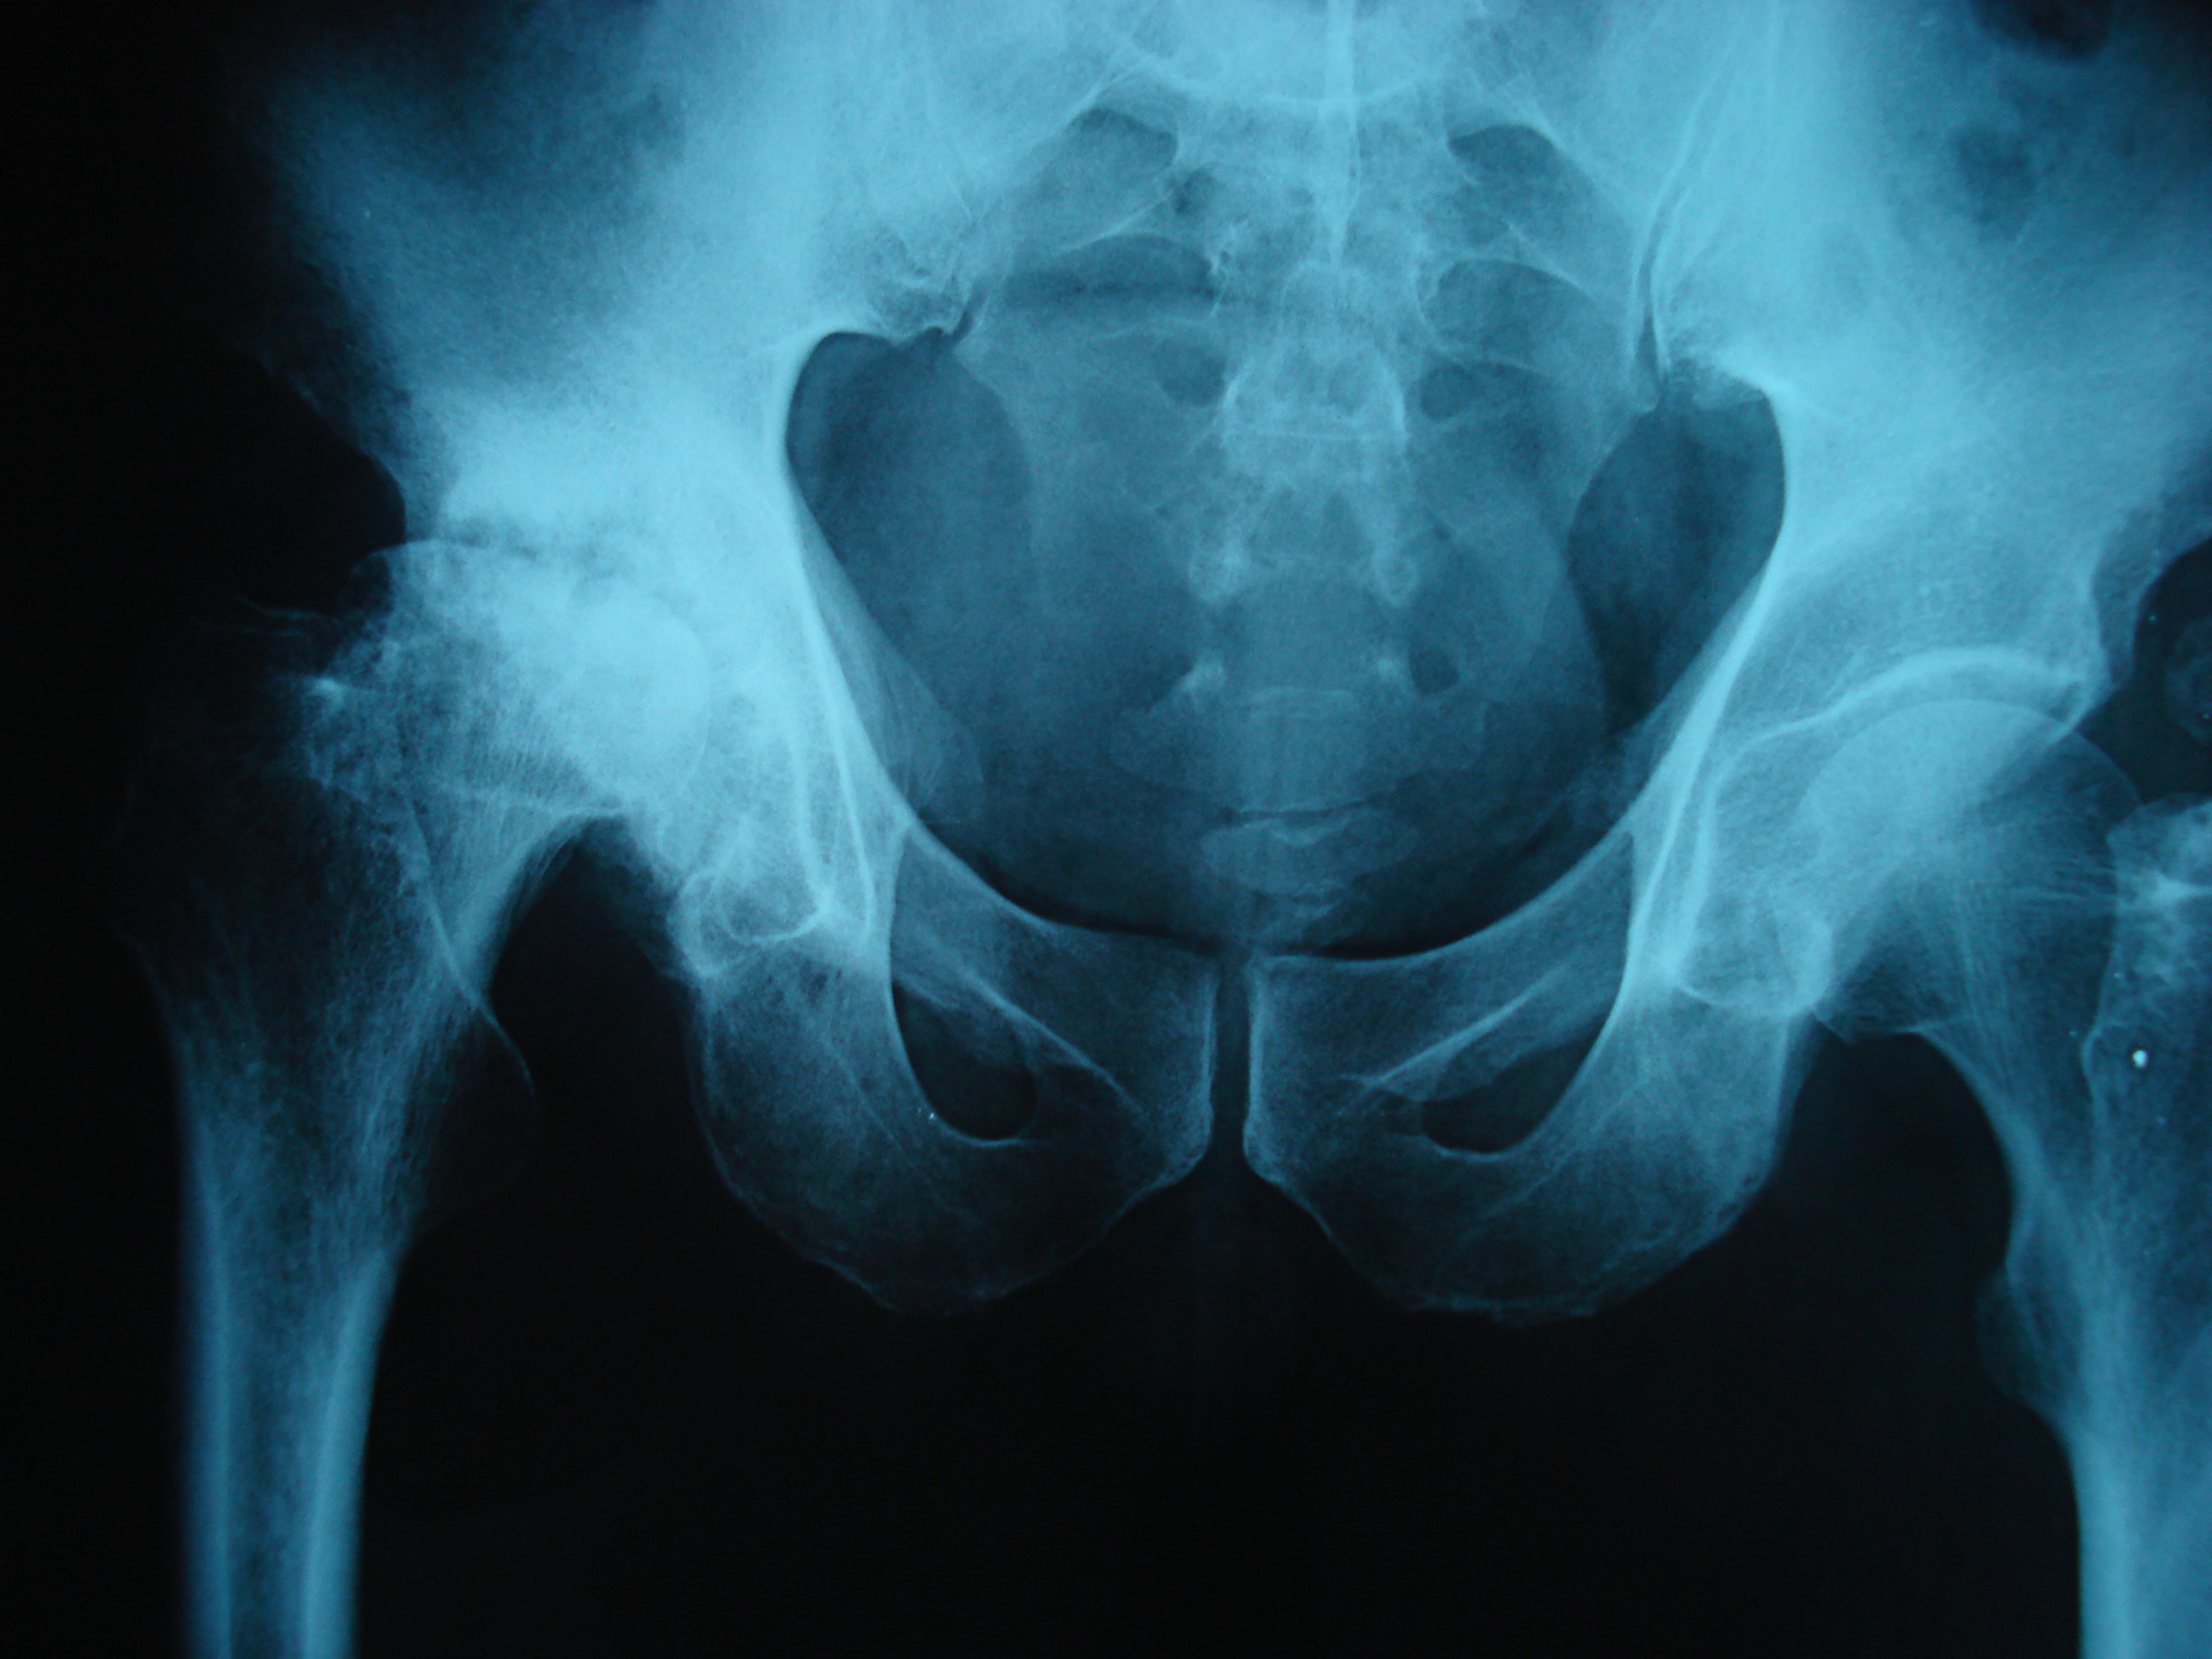

Kalça artrozu

• Konservatif tedavi( analjezik, kilo verme, egzersiz, baston kullanımı vs)

• Cerrahi tedavi